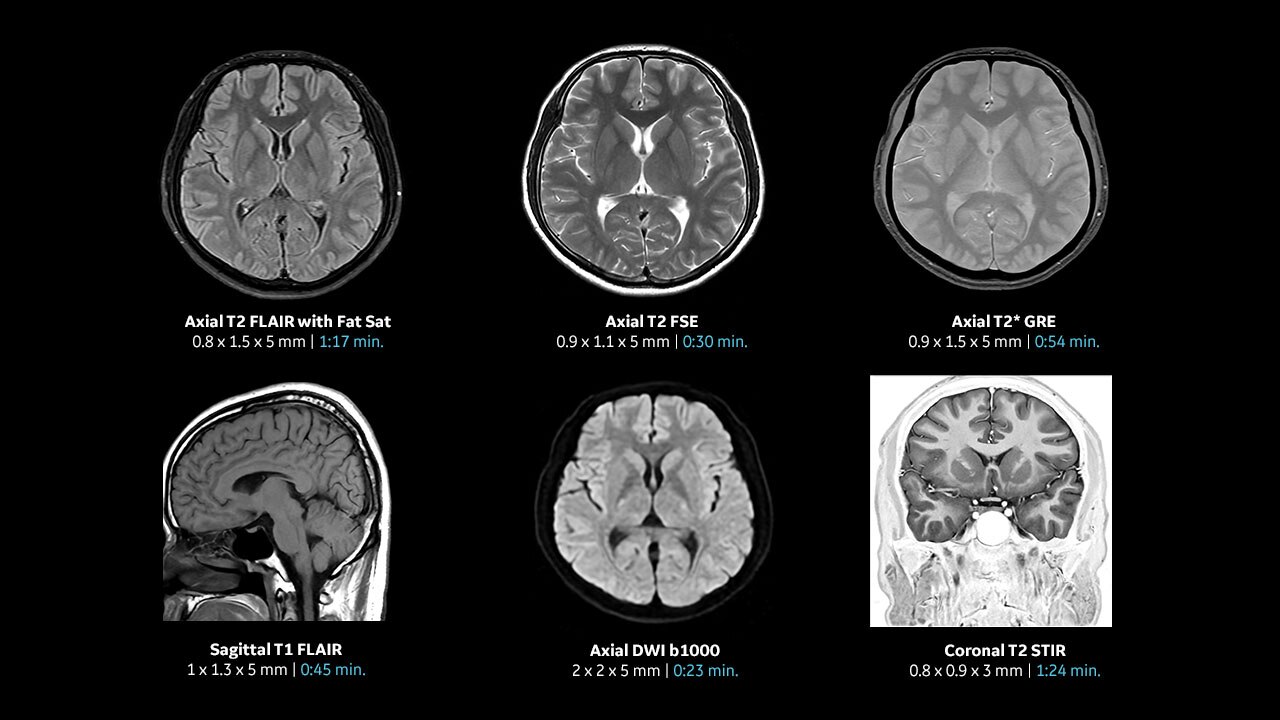

With access to the latest advanced AI technology, you can scan all anatomies and achieve pin-sharp images. Our pioneering Deep Learning-based reconstruction algorithm AIR™ Recon DL accelerates scan time and puts patients at ease.